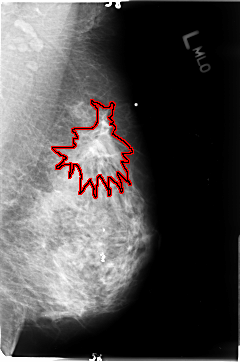

B_3048_1.RIGHT_MLO

FILE: B_3048_1.RIGHT_MLO.OVERLAY

TOTAL_ABNORMALITIES 1

ABNORMALITY 1

LESION_TYPE MASS SHAPE LOBULATED MARGINS CIRCUMSCRIBED-OBSCURED

ASSESSMENT 3

SUBTLETY 3

PATHOLOGY UNPROVEN

TOTAL_OUTLINES 1

BOUNDARY